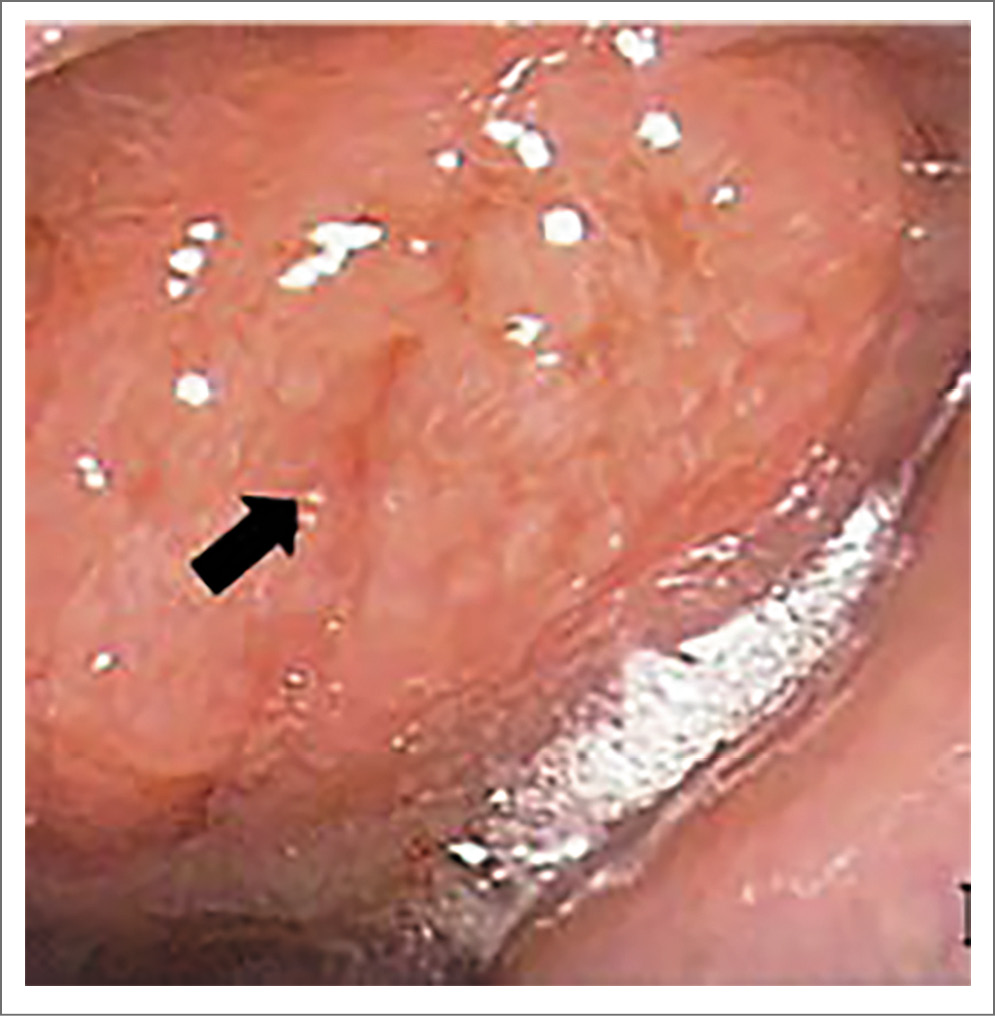

Пациент предоставил заключение врача-инфекциониста, данных о наличии герпесвирусной инфекции, инфекции, вызываемой вирусом Эпштейна–Барр, и цитомегаловирусной инфекции не получено. Пациенту назначена компьютерная и магнитно-резонансная томография околоносовых пазух для определения распространения патологического процесса, а также исключения инвазии в смежные анатомические области (рис. 2, 3). В предоперационном периоде под контролем эндовидеоскопического оборудования пациенту выполнен забор материала из свода носоглотки, верифицирован диагноз саркоидоза носоглотки (рис. 1, 4).

Рис. 1. Эндоскопическая картина пациента с диагнозом саркоидоза носоглотки.